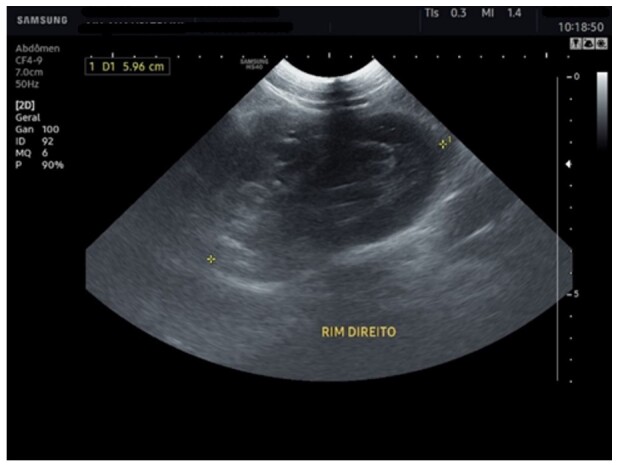

Abstract Image